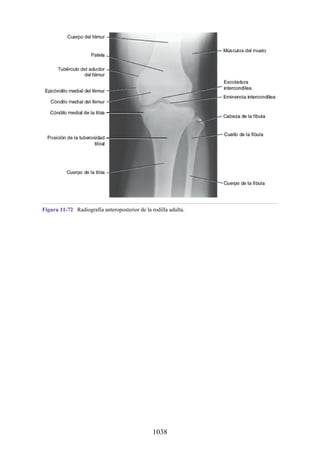

Aberturas hacia el atrio derecho

La sangre regresa al corazón desde la mitad superior del cuerpo a través de la